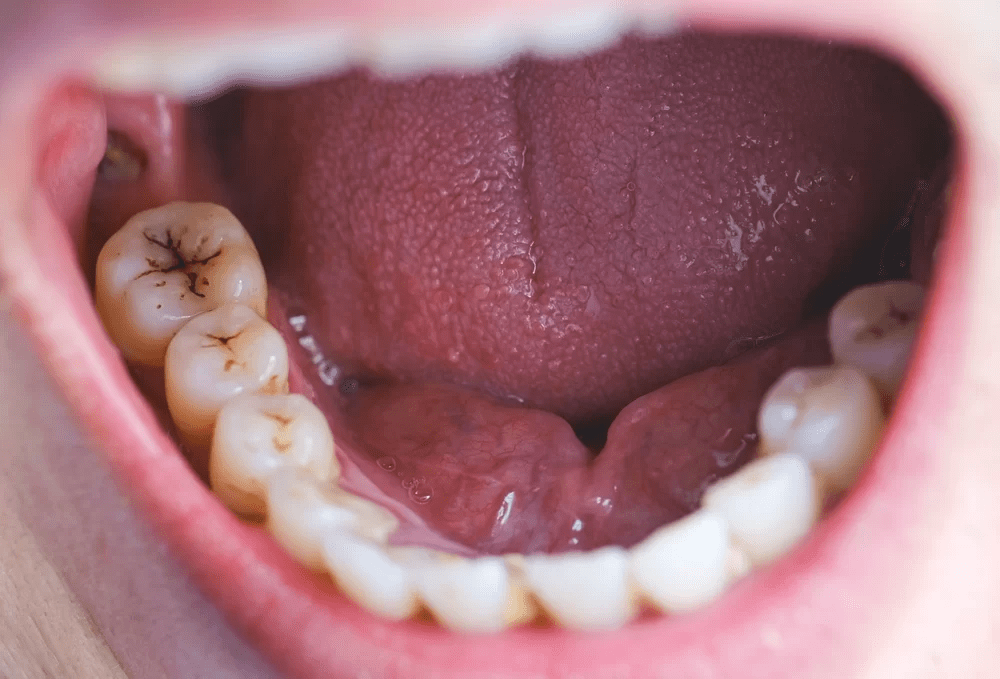

Cavities form when bacteria feast on sugars, producing acids that erode enamel. Sugary drinks, snacks, or even stress-induced grinding can speed this up. You might think brushing twice a day is enough, but many miss a key step. What’s the one thing your dental routine might be overlooking? Let’s explore a remedy that could make all the difference.

1. Fights Bacteria Like a Pro

Meet Sarah, a 47-year-old teacher who dreaded her dental checkups. Her mornings started with sensitivity that made her skip her favorite citrus fruits. Then she tried oil pulling. Swishing coconut oil for 10 minutes daily reduced her mouth’s bacteria, easing her discomfort. Studies, like one from the Journal of Traditional and Complementary Medicine, show coconut oil’s lauric acid can reduce harmful bacteria by up to 50%. Less bacteria, fewer cavities. But how does it feel to reclaim your smile?

3. Strengthens Your Enamel’s Defense

Picture biting into a crisp salad without flinching. Coconut oil’s fatty acids may create a protective barrier on enamel, slowing acid damage. A 2019 study found oil pulling reduced plaque buildup in 80% of participants after two weeks. You might be thinking, “Is this too good to be true?” It’s not a cure, but it supports your brushing routine. What else can this remedy do for your daily comfort?